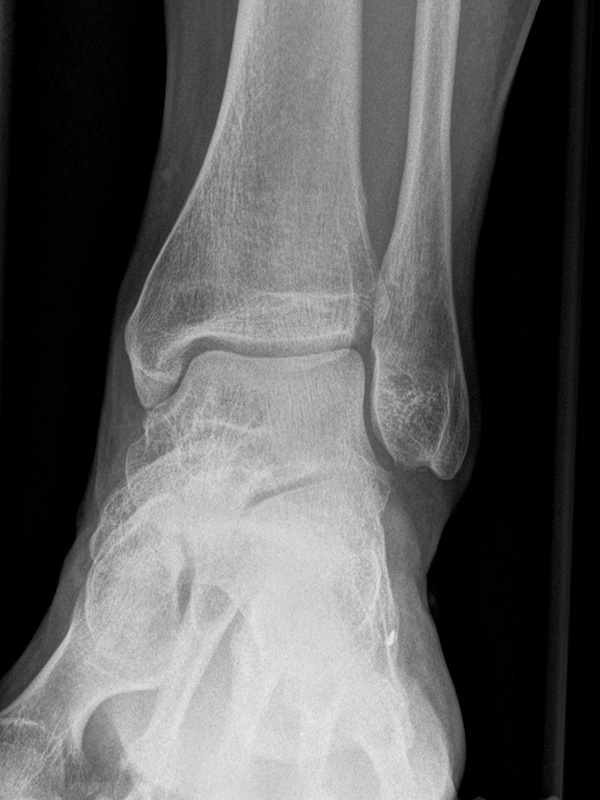

Sprunggelenk lateral ohne Belastung

Positionierung:

• Patient liegt auf dem Rücken und dreht den Fuß des aufzunehmenden Beins so nach innen, dass beide Malleolen genau übereinanderstehen.

• Die laterale Fuss-Seite liegt auf der Kassette, das Sprunggelenk ist 90° angewinkelt.

• Der Zentralstrahl wird zentral auf das Sprunggelenk gerichtet.

Kennzeichen des Röntgenbildes:

• Oberes und unteres Sprunggelenk sind rein seitlich abgebildet, inklusive Kalkaneus.

• Die Malleolen kommen übereinander zu liegen.

• Tibiagelenkfläche und Talusrolle werden exakt seitlich dargestellt, es kommt zu keinen Doppelkonturen.

• Die Fibula projiziert sich ins mittlere bis hintere Drittel der Tibiagelenkfläche.

• Die vordere und hintere Tibiakante, das Chopart-Gelenk und das Subtalargelenk kommen zur Darstellung.

• Das proximale Ende des Os metatarsale V ist mit abgebildet.

• Der Weichteilmantel (Achillessehne) ist erkennbar.

Besondere Bemerkungen zum Beispielbild:

• Patient mit anamnestisch chronischer OSG Instabilität.

• Ventral der Tibia findet sich ein abgebrochener Osteophyt.

Zur Vollansicht und zum Lesen der Bildbeschreibung bitte die Bilder anklicken.